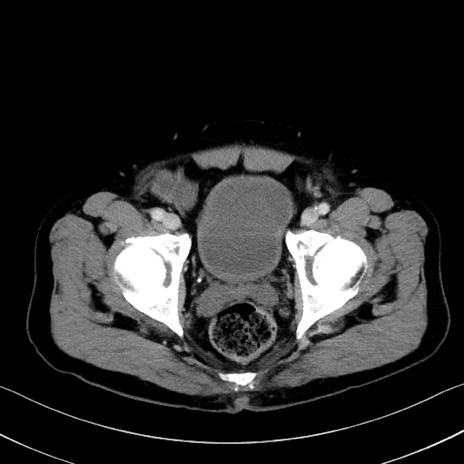

症例35(横断像)

【症例】70歳代 男性

【主訴】腹部膨満、嘔吐

【現病歴】昨日より腹部膨満感出現。本日増悪し、仙痛出現。嘔吐あり、受診。

【既往歴】糖尿病、胆摘後

【身体所見】BP 149/80mmHg、HR 74/min、BT 35.9℃、腹部:膨満、軟、圧痛なし。腸雑音減弱あり。上腹部正中切開瘢痕あり。

【データ】WBC 13500、CRP 1.72